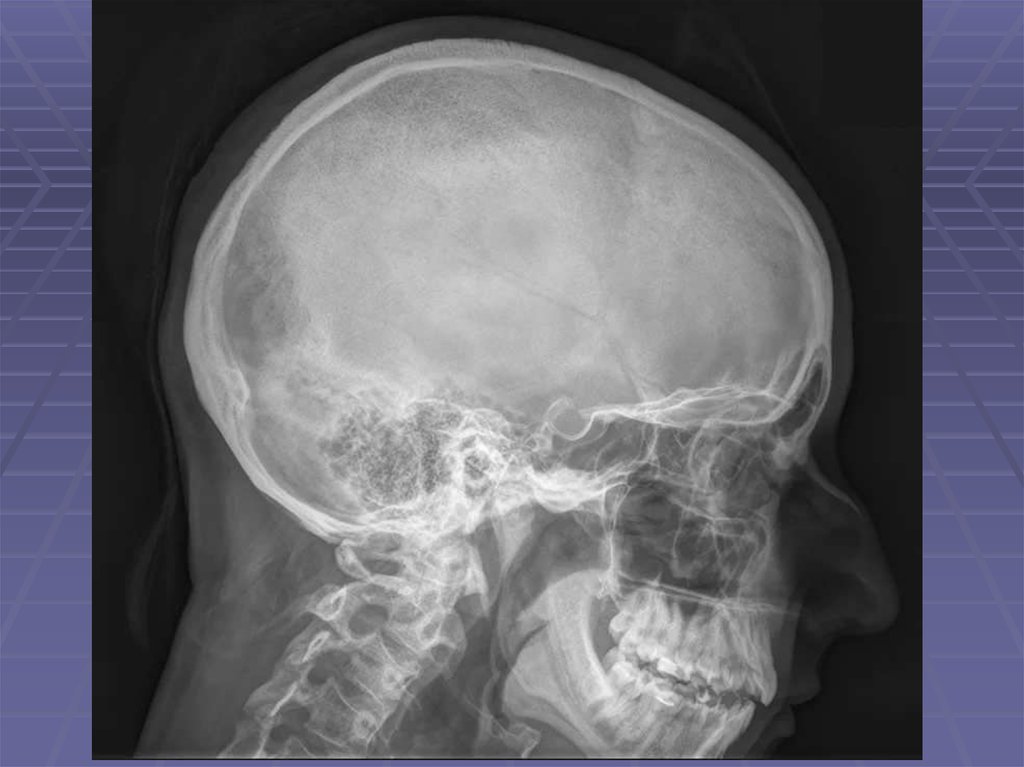

Череп